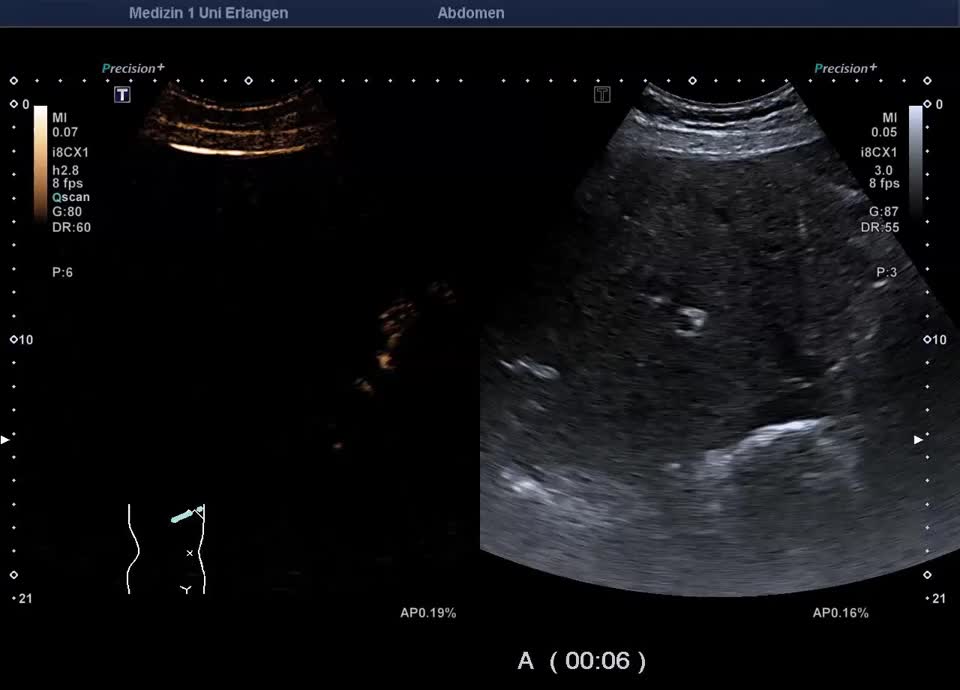

Kasuistik: 66-jähriger Patient mit seit der Jugend bekannter γ-GT-Erhöhung, sonographische Vorstellung zum Ausschluss eines cholangiozellulären Karzinoms. Sonographisch zeigt sich im B-Bild ein inhomogenes Leberparenchym mit diffus verteilten kleinen Kometenschweifartefakten im rechten Leberlappen. Das sonographische Bild ist vereinbar mit multiplen biliären Hamartomen (Von-Meyenburg Komplexe). Sie bestehen aus Zysten, die mit Gallengangsepithel ausgekleidet sind, und Bindegewebe, treten einzeln oder multipel auf und weisen typischerweise eine Größe von etwa 0,5–15 mm auf. Sonographisch stellen sie sich als echoreiche Noduli dar. Zum Ausschluss malignitätsverdächtiger Herdbefunde wurde eine kontrastmittelverstärkte Sonographie durchgeführt. Im CEUS zeigt das Leberparenchym in der portalvenösen und Spätphase homogenes Enhancement – die echoreichen Noduli sind isokontrastiert (Ausschluss Malignität). Die kleinen Zysten sind in allen Perfusionphasen nicht KM-aufnehmend. In Zusammenschau der Bildgebung und der bekannten γ-GT-Erhöhung besteht kein Anhalt für eine maligne Lebererkrankung. Eine einmalige sonographische Verlaufskontrolle wurde vereinbart.